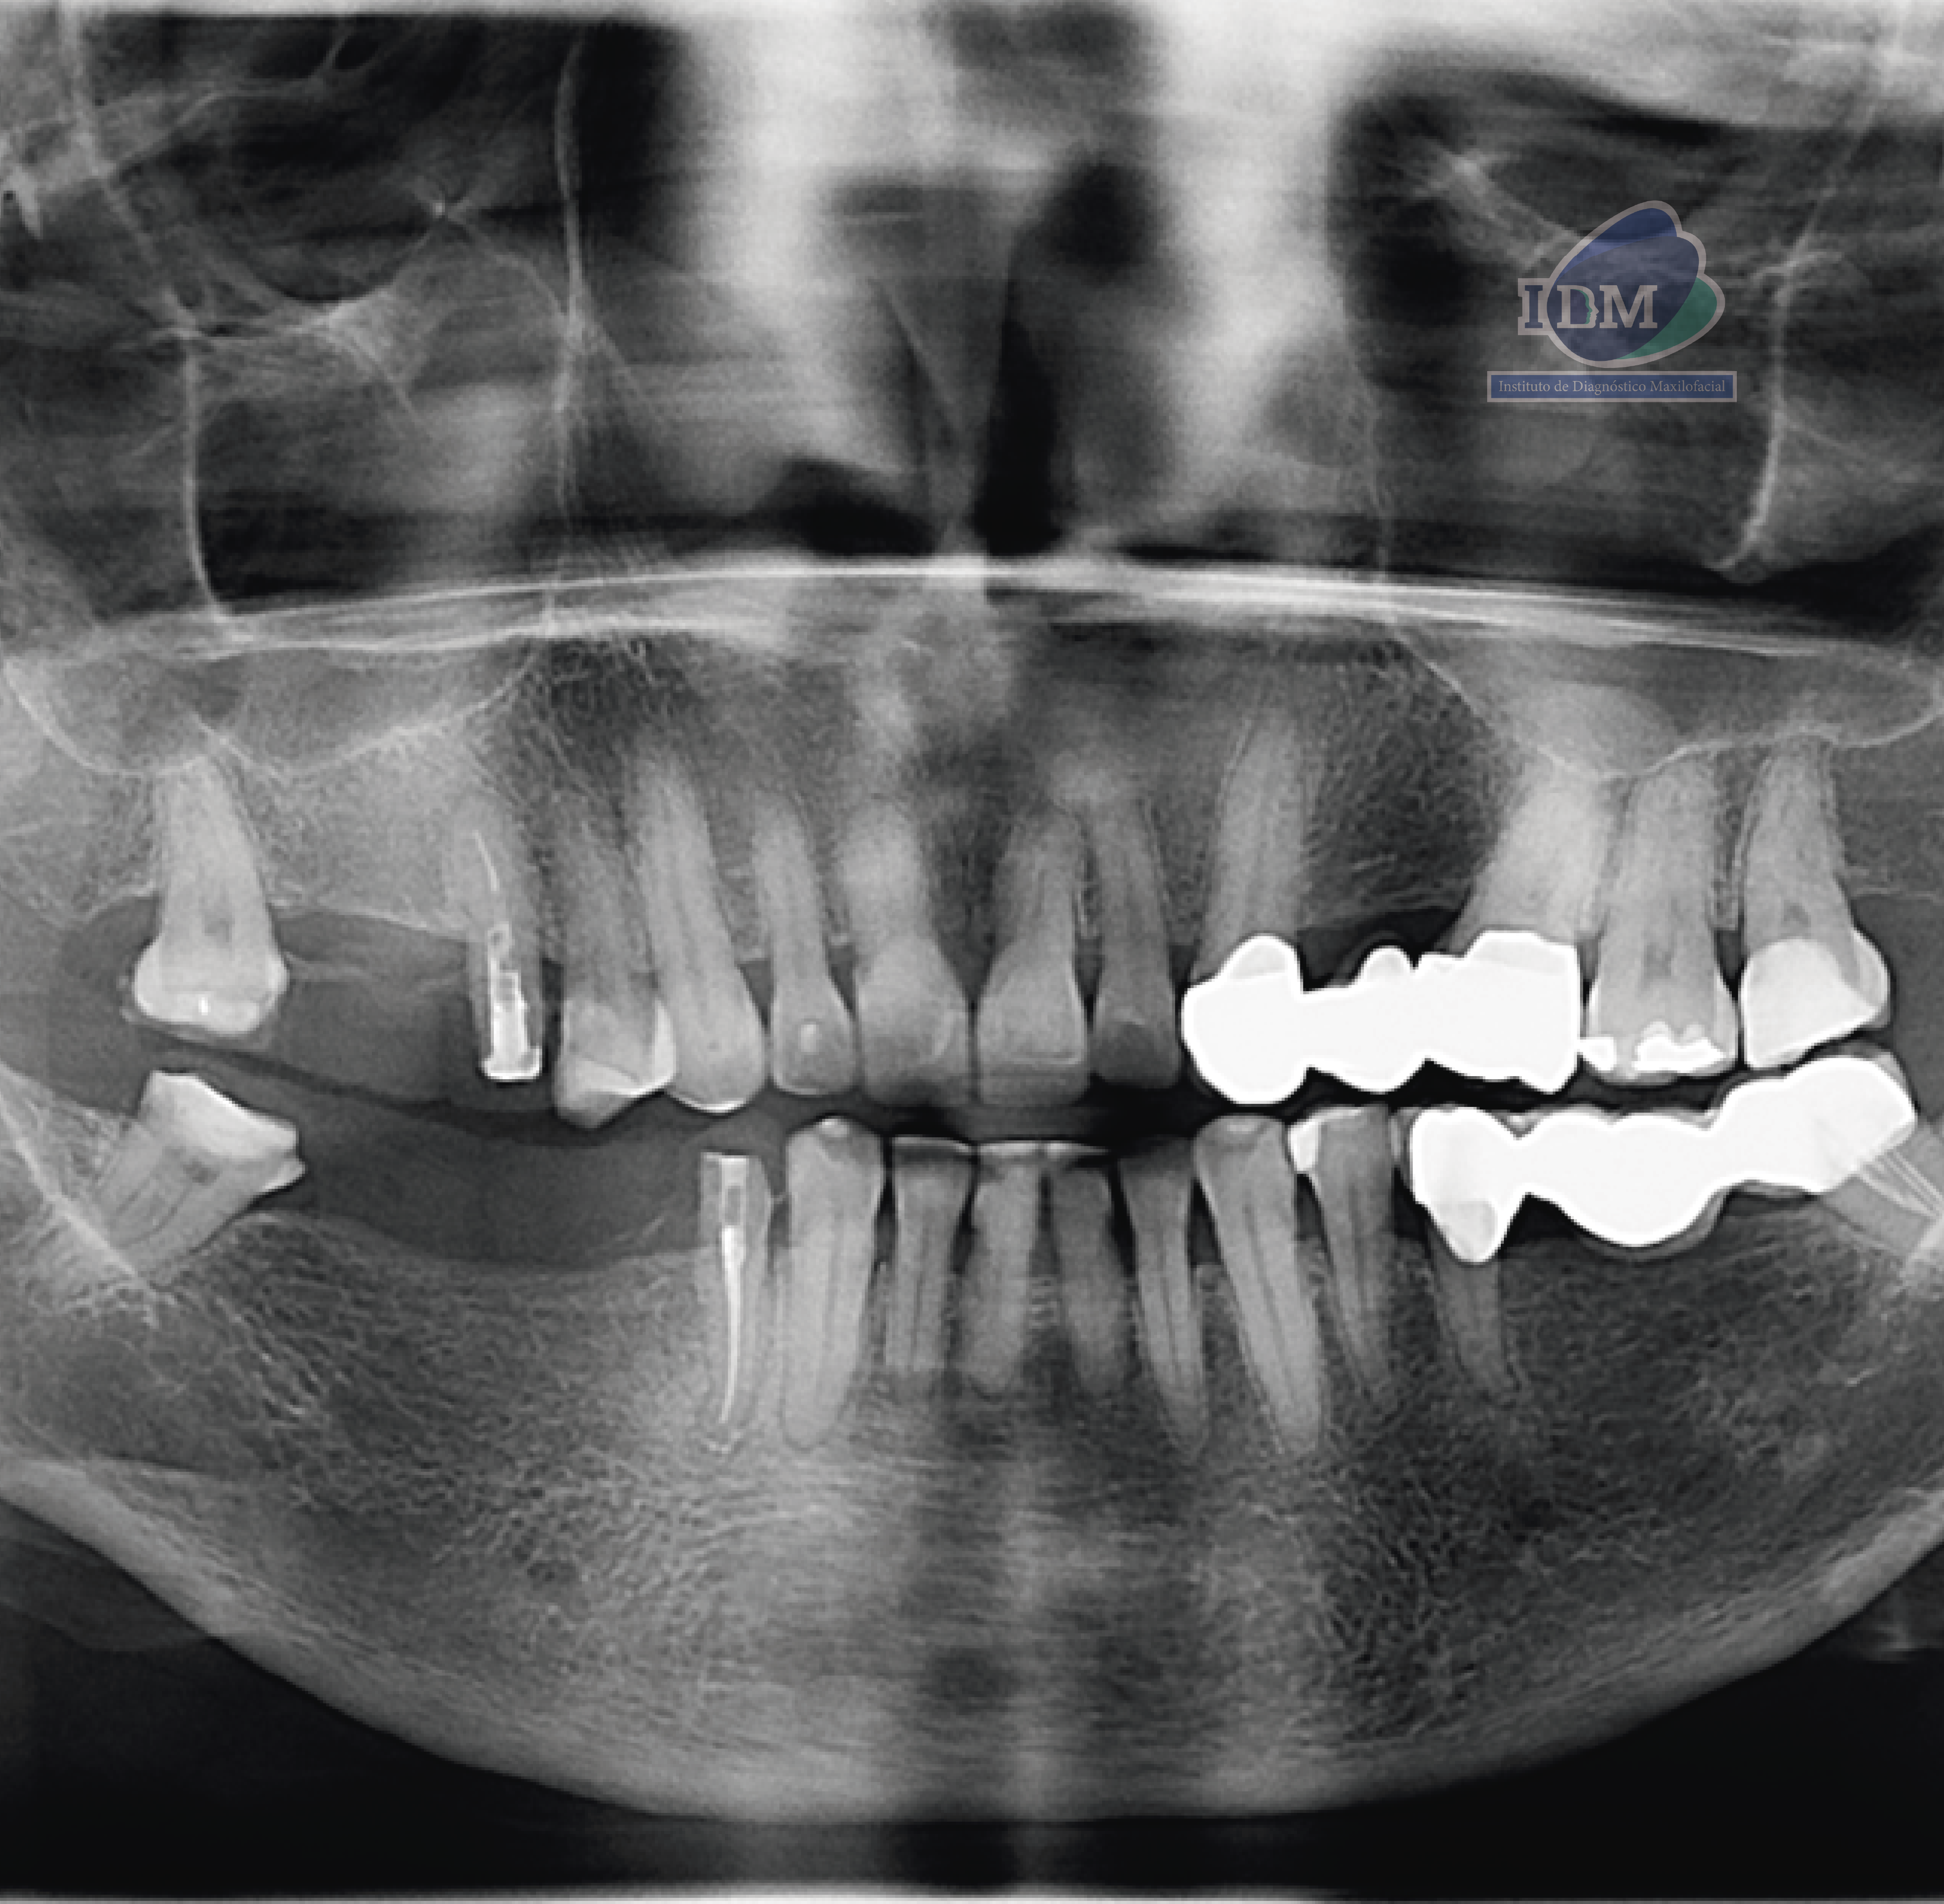

Paciente masculino de 55 años, es referido al Instituto de Diagnóstico Maxilofacial – IDM (Sede Surco) para planificación de implantes dentales. Radiografia Panorámica En la